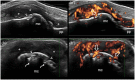

Bone erosions are the hallmark of structural damage in rheumatoid arthritis (RA). Among imaging techniques, ultrasonography (US) has emerged as an accurate, reliable, repeatable, low-cost and non-invasive imaging modality to detect erosive changes in RA. However, small interruptions of the cortical bone detectable by last generation US equipment do not necessarily represent bone erosions. According to the available data, in addition to cortical bone interruption itself, only a few morphological US findings have been proposed to define RA bone erosions. However, other additional features may be considered to facilitate the interpretation of US cortical bone interruptions in RA. These could be summarised using the following four domains: size, site, shape and scenery. This hypothesis article provides a critical literature review of US features characteristic of RA bone erosions and pictorial evidence supporting the potential role of a morphological analysis in the US identification of bone erosions in RA patients.

Plain language summary: The ultrasonographic morphology of cortical interruptions is helpful for the identification of bone erosions in rheumatoid arthritis: the "four Ss" approach Bone erosions are characteristic features of rheumatoid arthritis. They are associated with a more aggressive disease and with irreversible physical disability. In recent years, ultrasonography has emerged as an accurate and reliable technique for the detection of bone erosions, that appear as interruptions of the cortical bone with variable size. However, cortical bone interruptions do not necessarily represent bone erosions. Since bone erosions represent the earliest evidence of the destructive behaviour of RA, their identification is crucial.Besides the cortical interruption itself, only a few morphological ultrasonographic features were proposed to characterise bone erosions in rheumatoid arthritis.We believe that a morphological approach, including size, site, shape and scenery, may be considered to facilitate the interpretation of ultrasonographic cortical bone interruptions in rheumatoid arthritis.In this hypothesis article we carried out a critical review of the scientific literature and provided extensive pictorial evidence of the ultrasonographic spectrum of cortical interruptions supporting the potential role of considering the "four Ss" for the ultrasonographic identification of bone erosions in rheumatoid arthritis.